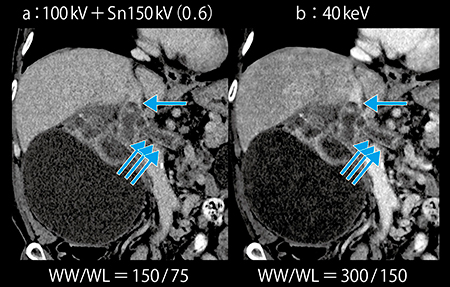

通常,静脈の評価は皮質髄質相で行うが,静脈腫瘍塞栓は遅いタイミングで評価する必要がある。本症例は体格も大きく,かつ造影剤量も40mLと少ないため,腎実質相での静脈造影効果は不明瞭となってしまう。100kV+Sn150kV画像では静脈の濃染が評価困難であった。しかし,Mono+の40keV画像では造影効果が向上し,腎静脈および下大静脈内の腫瘍塞栓が明瞭に認められた(図3)。静脈のCT値が上昇したことで,十分にウインドウレベルを広げた状態でも病変が観察しやすくなっている。

図3 症例1:Mono+の40keV画像による低造影剤量での静脈描出

続いて撮影した腎実質相および排泄相では造影剤量が不十分であるが, Mono+の40keV画像により,ノイズが増加することなく腎実質の造影効果が増強し,腫瘍と腎実質のコントラストが確認できた(図6)。また,わずかに尿路に排泄された造影剤と腫瘤とのコントラストも得ることができた(図7 b↓)。

図6 症例2:Mono+の40keV画像による造影剤20mLでの腎実質相の描出